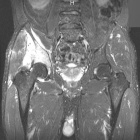

D.R. - 65 year old male, c/o worsening right hip/buttock pain for six months. Pain is constant, worse with activity. Tylenol helps a bit. No F/C or constitutional sx.

PMH: Crohn's disease, nephrolithiasis, prostate infection, gallstones

Zoom image: Radiological image Radiological image.